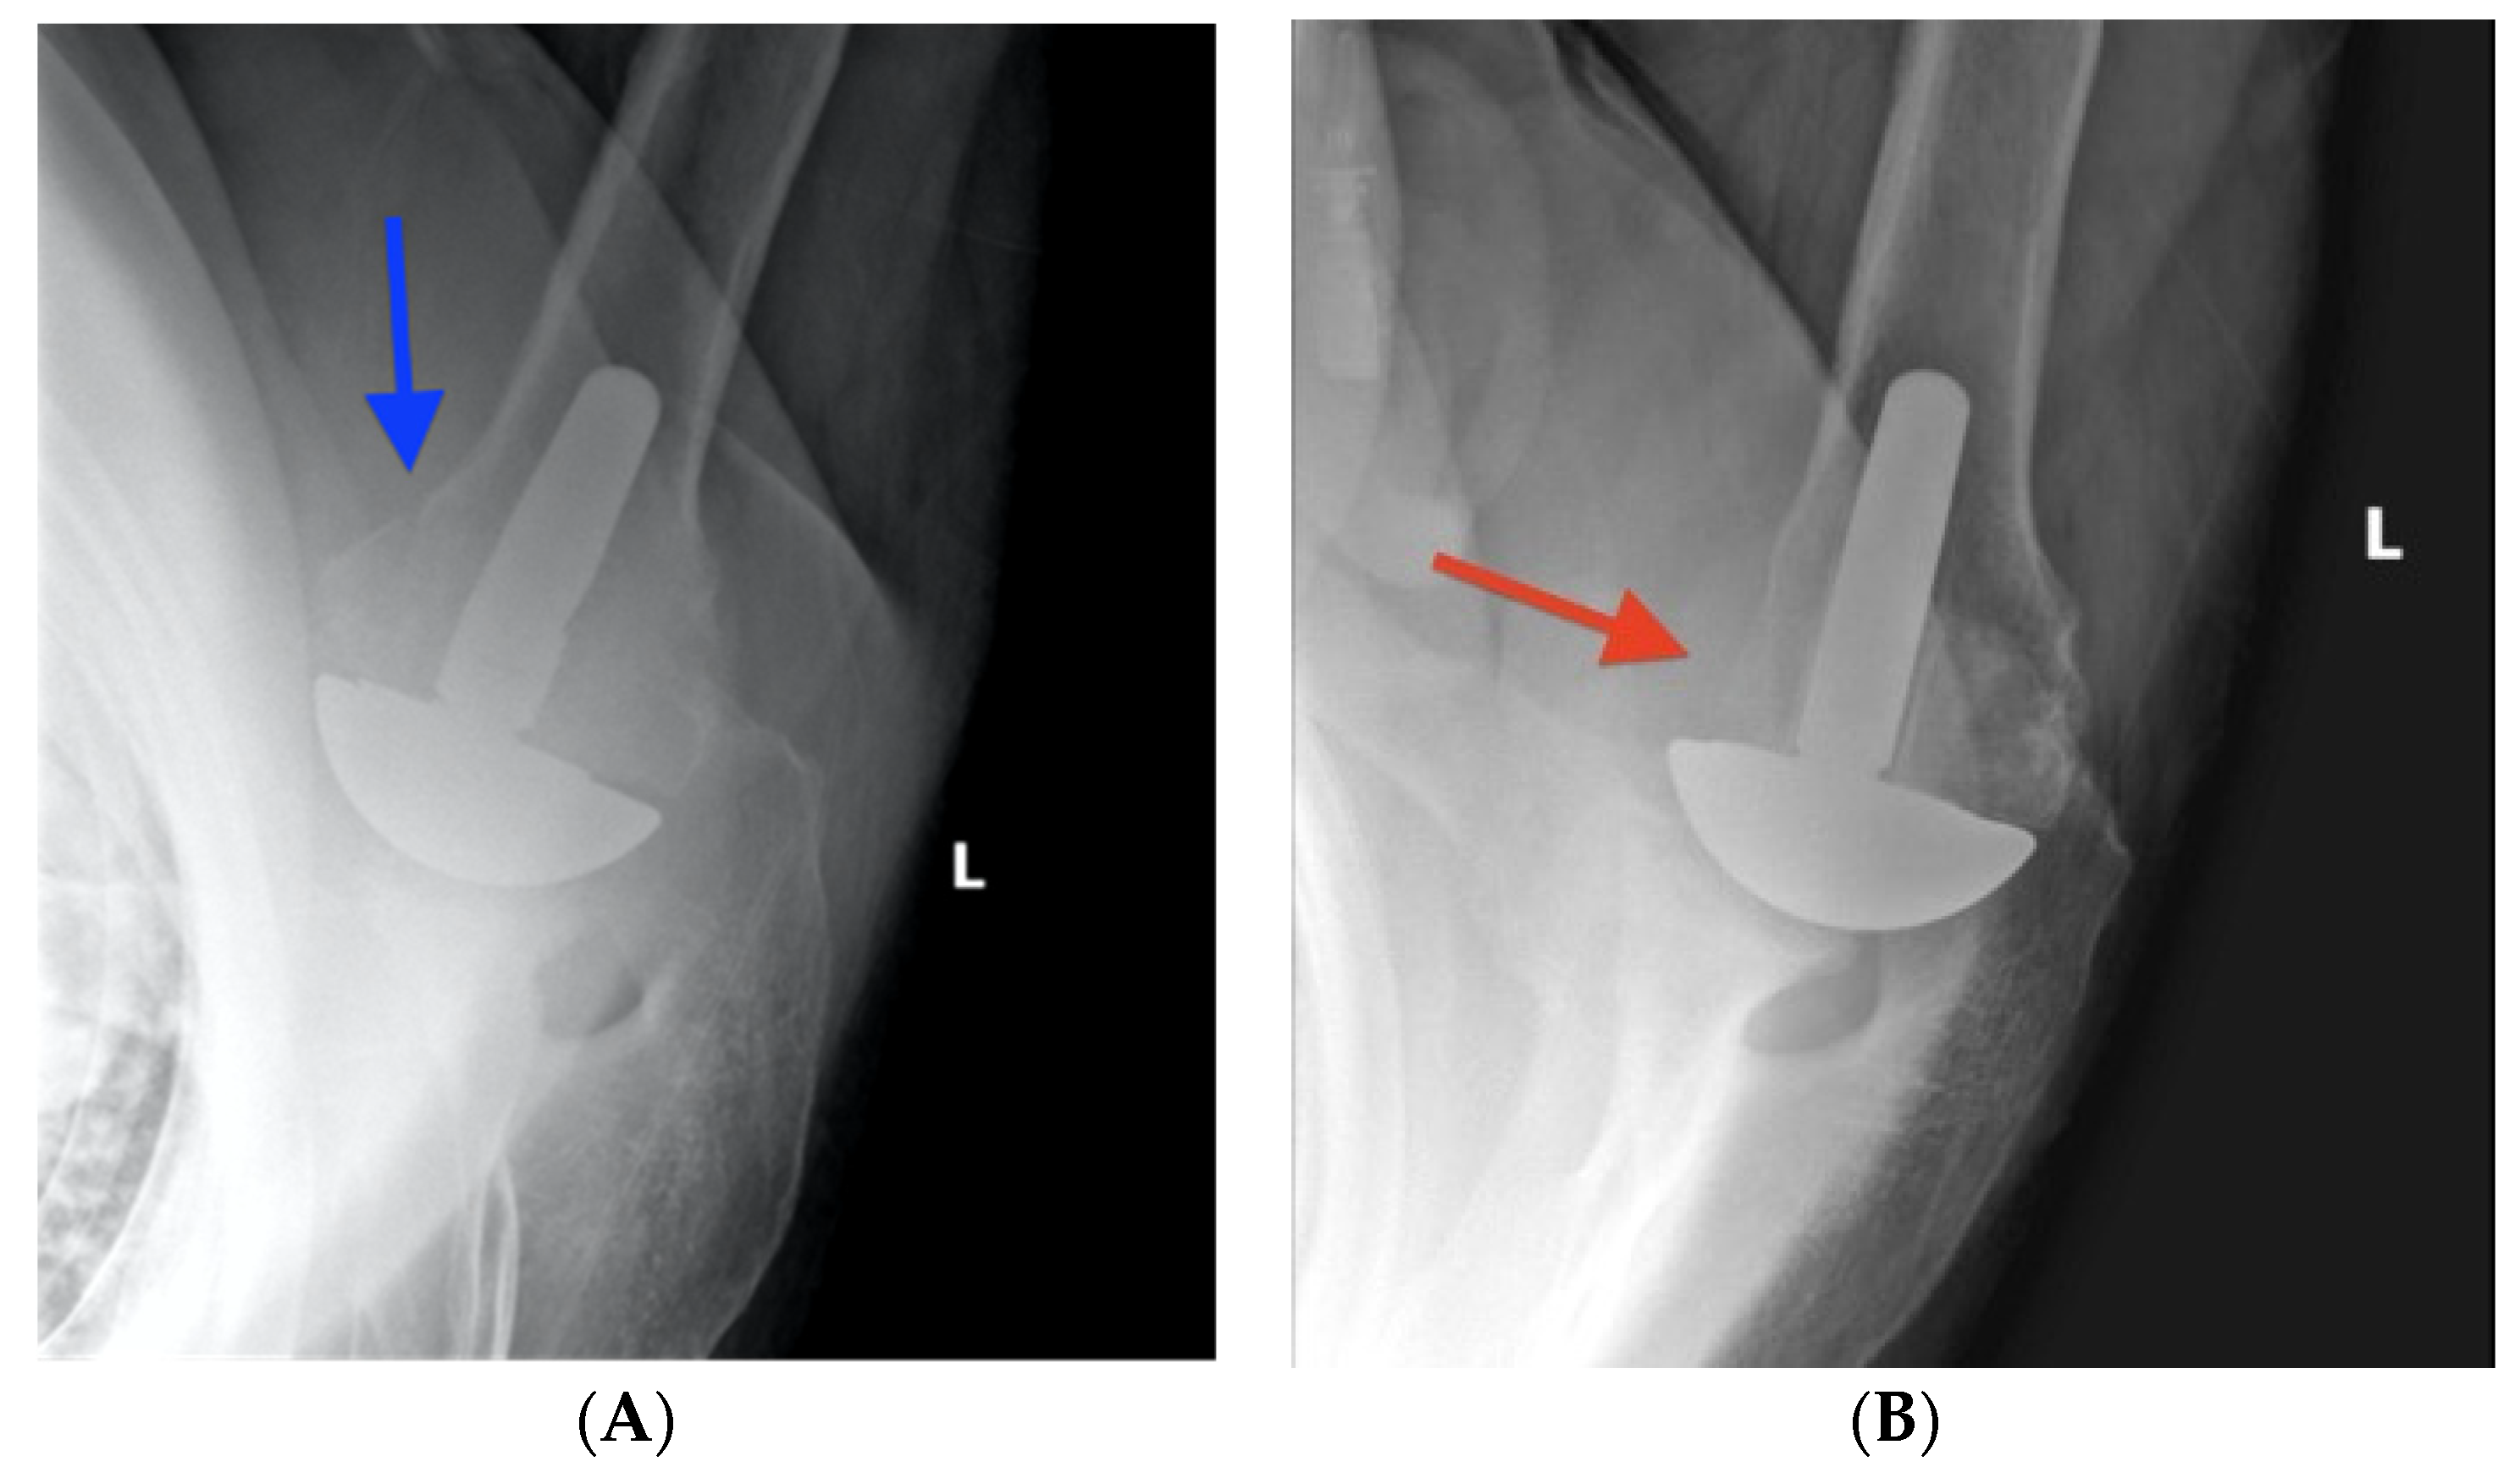

2.3. Radiographic Evaluation

- Small, K.M.; Siegel, E.J.; Miller, L.R.; Higgins, L.D. Imaging Characteristics of Lesser Tuberosity Osteotomy after Total Shoulder Replacement: A Study of 220 Patients. J. Shoulder Elb. Surg. 2014, 23, 1318–1326. [Google Scholar] [CrossRef]

- Levy, J.C.; DeVito, P.; Berglund, D.; Vakharia, R.; Moor, M.; Malarkey, A.; Polansky, S. Lesser Tuberosity Osteotomy in Total Shoulder Arthroplasty: Impact of Radiographic Healing on Outcomes. J. Shoulder Elb. Surg. 2019, 28, 1082–1090. [Google Scholar] [CrossRef]